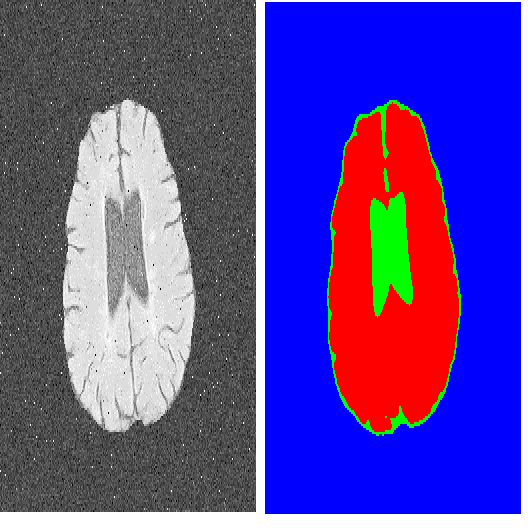

We consider a variational model for single-image super-resolution based on the assumption that the gradient of the target image is sparse. We enforce this assumption by considering both an isotropic and an anisotropic $\ell^0$ regularisation on the image gradient combined with a quadratic data fidelity, similarly as studied in [1] for general signal recovery problems. For the numerical realisation of the model, we propose a novel efficient ADMM splitting algorithm whose substeps solutions are computed efficiently by means of hard-thresholding and standard conjugate-gradient solvers. We test our model on highly-degraded synthetic and real-world data and quantitatively compare our results with several variational approaches as well as with state-of-the-art deep-learning techniques. Our experiments show that $\ell^0$ gradient-regularised super-resolved images can be effectively used to improve the accuracy of standard segmentation algorithms when applied to QR and cell detection, and landcover classification problems, in comparison to the results achieved by other approaches.

翻译:我们根据目标图像梯度稀少的假设,考虑单一图像超分辨率的变异模型。我们通过在图像梯度上考虑异位和异位元值的常规化,同时考虑对图像梯度和二次数据忠实度的常规化,我们考虑这一假设,类似于在[1]中研究的一般信号恢复问题。关于模型的数值实现,我们建议一种新型高效的ADMM 分离算法,其子步骤解决方案通过硬存储和标准共振分级解算法有效计算。我们测试了我们关于高度降解合成和真实世界数据的模型,并以数量方式将我们的结果与几种变异方法以及最新的深层学习技术进行比较。我们的实验表明,在应用到QR和细胞检测以及土地覆盖分类问题时,可以有效地使用$(ell_0美元)的梯度正规化超溶解图像来提高标准分解算法的准确性,并与其他方法取得的结果相比较。